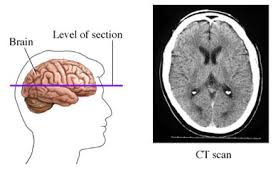

Las punzadas en la cabeza suelen ser causadas en la mayoría de los casos por las patologías mencionadas anteriormente que deben ser apropiadamente diagnosticadas por un neurólogo quien indicará el tratamiento adecuado para evitarlas. Hola estoy sintiendo punzadas que me duran de 3 a 4 segundos en la cabeza son como quemonazos con ardor al lado derecho me dan por hay 3 al diaya me hize un ct scan de la cabeza y me salio pere salio perfecto no se que pueda ser el neurologo me receto gabapentin pero la droga me callo muy mal y deje de tomarla porfavor ayundenme que pudiera ser se los. Un dolor de cabeza es un dolor o molestia en la cabeza el cuero cabelludo o el cuello.